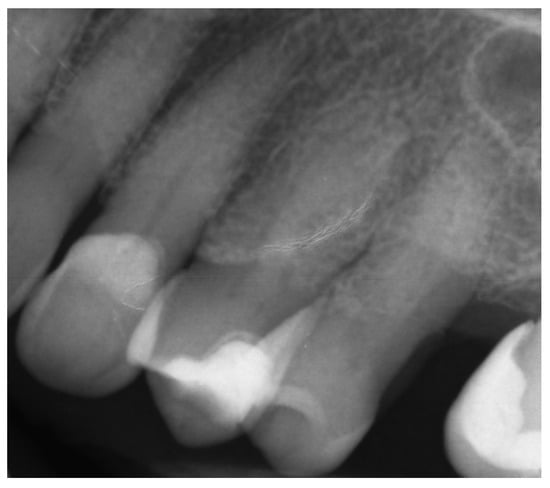

A 39-year-old male patient was referred to an endodontic specialist for the treatment of a maxillary left central incisor (tooth 21) before prosthetic treatment. Endodontic treatment had been initiated by the referring dentist, but as it was impossible for the clinicians to localize the root canal under the optical microscope, the treatment could not be completed, and the patient was referred to a specialist. The patient’s medical history revealed the absence of any systemic disorders or allergies. The dental history revealed trauma to the maxillary anterior region in childhood and subsequent gradual discolouration of the maxillary left central incisor. The patient presented with no complaints. Clinically, there were no pain or sensitivity to percussion or palpation. Tooth mobility was not increased. The tooth was restored by the referring dentist with a temporary restoration (composite resin) and showed no response to the pulp sensibility test (cold test). The radiograph and CBCT images showed that the endodontic treatment was initiated with wide access in the coronal part and confirmed root canal obliteration (Figure 16). After discussing the high probability of perforation and further tooth substance loss, an endodontic guide was designed.

Figure 16. The failed wide access in the coronal part and root canal obliteration on (a) X-ray and (b) CBCT images.